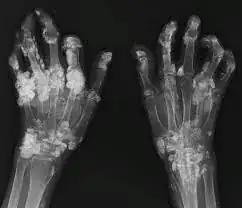

Excess calcification of bone, or calcification of soft tissues is actually detrimental to function and wellbeing. Take these arthritic hands for example:

enter image description here

Those are crippled hands, disfigured and unable to function because of excess calcification.